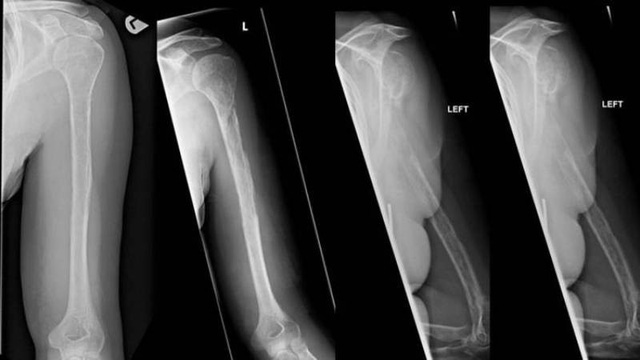

Sau 18 tháng ròng, cuối cùng các nhân viên y tế cũng đưa ra câu trả lời. Bằng cách quan sát các ảnh chụp X quang, bác sĩ nhận thấy xương trong cơ thể người phụ nữ mờ dần sau mỗi lần quét. Nhiều thử nghiệm được tiến hành cũng đã xác nhận rằng xương của bệnh nhân biến mất theo nghĩa đen. Kỳ lạ thay, các mạch máu lại tăng trưởng thay thế cho mô xương của cô.

Xương bệnh nhân mờ dần trong ảnh chụp X quang